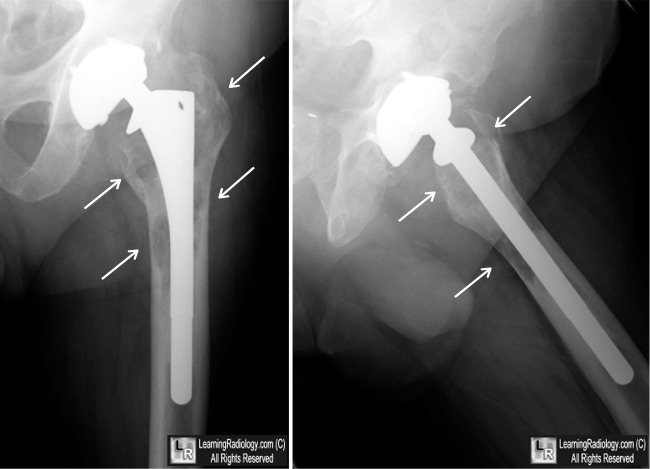

Diagnosis?

Cause?

Particle disease (aka aggressive granulomatosis).

An osteolytic histiocytic response of the bone to small polyethylene particles shed from the articular lining of orthopedic hardware. Look for abnormal liner wear, evident by superiorly malpositioned femoral head component in this case. May be asymptomatic until it is enough to cause loosening.